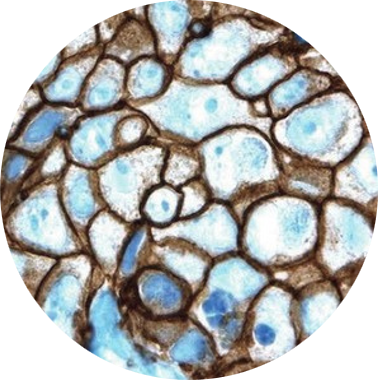

Exame Imuno-Histoquímico

Imuno-histoquímica é a técnica que aplica anticorpos específicos presentes em cortes histológicos, em associação com métodos de detecção altamente sensíveis para revelação da ligação antígeno (em geral, marcador tumoral) e anticorpo.

A aplicação desta técnica, em associação com a experiencia do patologista como morfologista, tem grande auxilio na definição diagnóstica e na definição de melhor tratamento para os pacientes.

O Lapac dispõe de uma variedade de anticorpos que permite avaliação diagnostica, prognostica e preditiva nas mais diversas patologias. As principais indicações clínico diagnósticas para o exame de Imuno-histoquímico são: